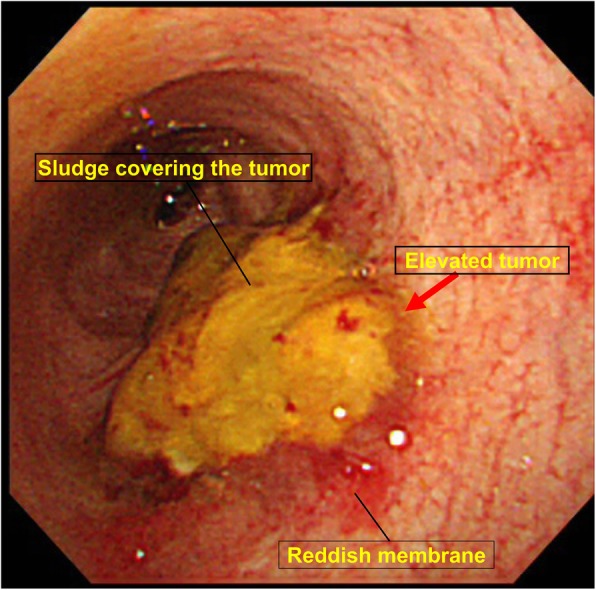

A 64-year-old man presented to our hospital with upper abdominal pain, jaundice, and anorexia. He had diabetes and was a social drinker but a lifetime non-smoker. Computed tomography (CT) scan revealed a dilated CBD, and acute cholangitis was suspected. The patient was referred to our hospital and admitted to the gastroenterology department for further investigation and treatment. Initial laboratory examinations revealed a white blood count (WBC) of 9770/μL, hemoglobin of 12.4 g/dl, increased C-reactive protein (CRP) of 5.47 mg/dl, total bilirubin of 7.75 mg/dl, AST/ALT of 176/281 IU/L, alkaline phosphatase of 815 IU/L, and ɤ-GTP of 132 IU/L. The serum tumor markers carcinoembryonic antigen (CEA) was within the normal range at 2.6 ng/ml and cancer antigen 19–9 (CA19–9) was elevated at 1162 U/ml. Both hepatitis B surface antigen (HBsAg) and antibodies to hepatitis C virus (anti-HCV) were negative. A plain CT scan on admission showed a high-density accumulation spreading throughout the CBD, and the entire CBD was dilated (Fig. 1). Gastroenterologists performed endoscopic retrograde cholangiopancreatography (ERCP) and endoscopic sphincterotomy (EST), during which a hematoma in the CBD was discovered. This revealed the reason for obstructive jaundice was not choledocholithiasis but the hematoma, which was subsequently drained through the incised Vater’s papilla (Fig. 2). A few days later, enhanced CT scan and magnetic resonance cholangiopancreatography (MRCP) were performed, and they showed improved dilation of the CBD and enhanced wall thickness of the bile duct measuring 25 × 10 mm at the union of the cystic and common hepatic ducts (Figs. 3 and 4). A cholangioscope detected an elevated tumor covered by sludge in the CBD (Fig. 5). The mucous membrane around the tumor showed redness and a malignant tumor was suspected. The result of the tumor biopsy revealed no malignant features in the histology, but the possibility of CC could not be denied from the macroscopic findings. We were consulted for surgical resection and performed an extrahepatic bile duct resection and cholecystectomy. Intraoperative rapid pathological diagnosis was performed, and we confirmed that the surgical margins in both the pancreatic and hepatic sides were cancer-free. The postoperative course was uneventful. The resected tumor had irregular elevated mucosa with an ulcerated lesion (Fig. 6a). The pathological examination of the resected tumor revealed that the ulcerated lesion had inflammatory granulation tissue; however, it did not contain the components of invasive carcinoma (Fig. 6b). Many consecutive intraepithelial micropapillary lesions spread around the ulcerated lesion, and the epithelial cells showed increased nucleus-to-cytoplasm ratio, nuclear hyperchromasia, and architectural atypia (Fig. 6c). The pathological diagnosis was BilIN-1 to -2. It also revealed that the BilIN-1 lesion spread through both the pancreatic and hepatic margins. Immunohistochemical staining showed that S100P was slightly expressed in the cytoplasm and MUC5AC was positive, while MUC1 was negative and p53 was not overexpressed (Fig. 6d–g).